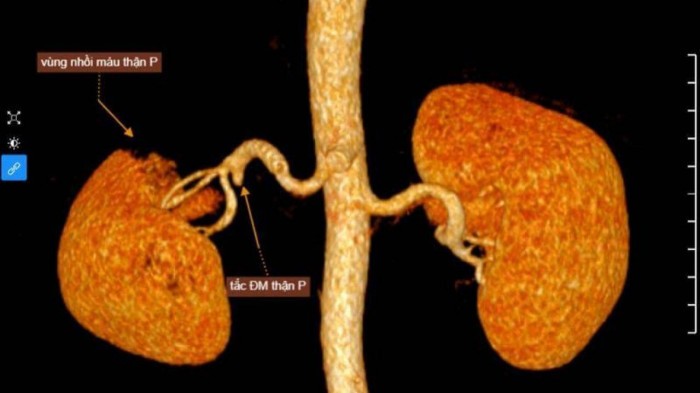

Tuy nhiên, sau đó, BS Tuyến quyết định chỉ định thêm chụp cắt lớp vi tính ổ bụng có tiêm thuốc cản quang, nhằm xác định rõ nguyên nhân gây đau bụng. Hình ảnh chụp cắt lớp vi tính (CT-Scanner) ổ bụng cho thấy hình ảnh nhồi máu thận phải do tắc một nhánh của động mạch thận. Ngay sau đó bệnh nhân được nhập viện điều trị kịp thời. Sau 7 ngày, tình trạng sức khỏe của bệnh ổn định và hết đau bụng.

Nhồi máu thận là tình trạng thiếu máu nhu mô thận do sự tắc nghẽn hoàn toàn hoặc một phần dòng máu đến thận. Nhồi máu thận thường xảy ra một bên, do nguyên nhân tắc động mạch thận.